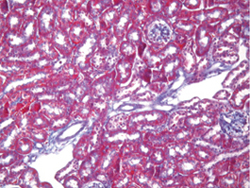

• マッソントリクローム染色(fig.2

膠原線維を染色する方法で、膠原線維と筋線維を染め分けるのが特徴です。

核をヘマトキシリンで染め、細胞質を赤く、膠原線維を青く染めるので、3色染色(トリクローム)と呼ばれます。

分子量の異なる色素を用いての染色で、ヘマトキシリンで核が青紫色に染まり、その後に拡散速度の大きい小色素分子(酸フクシン、ポンソーキシリジン)が細胞の細網孔へ浸透して赤色に染まり、次いで拡散速度の小さい大色素分子(アニリン青)が膠原線維の粗構造に入り込み、青色に染まります。